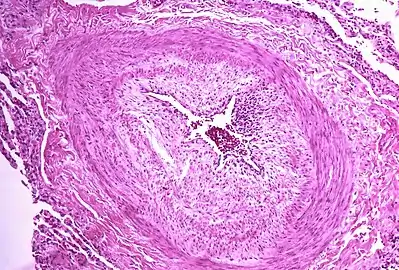

Micrograph showing arteries in pulmonary hypertensive with marked thickening of the walls.